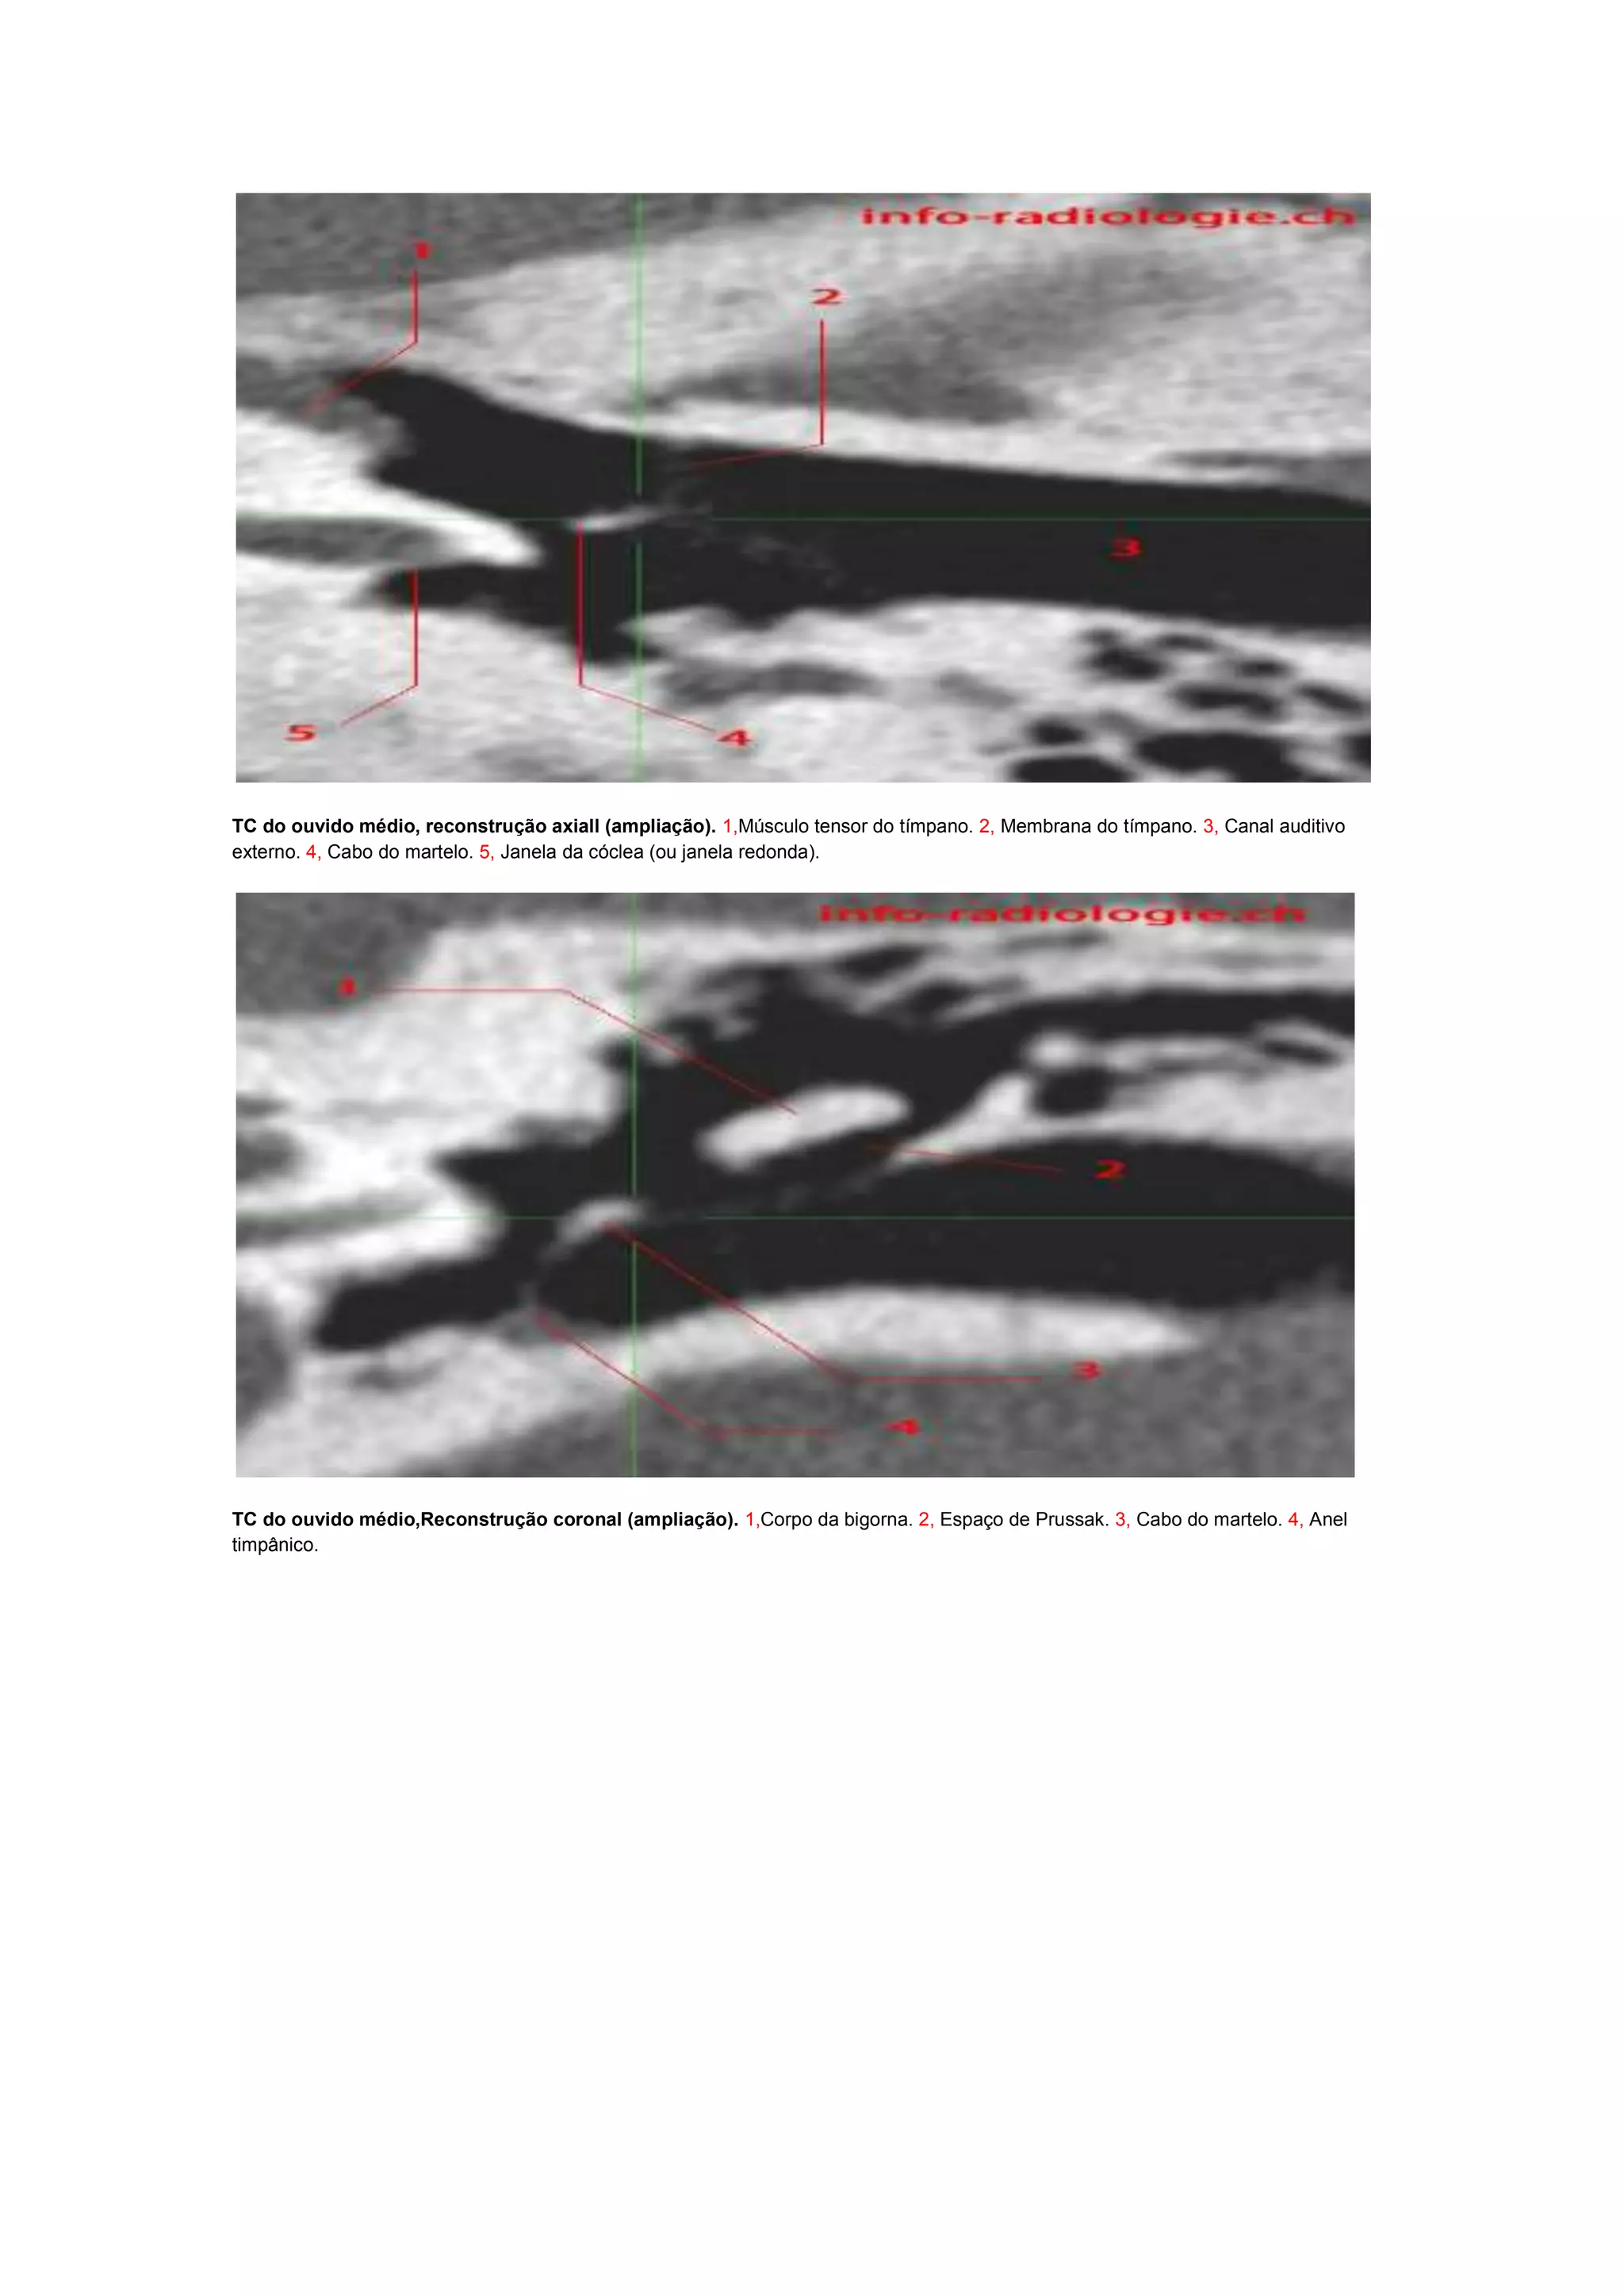

As imagens mostram cortes axiais, coronais e sagitais do ouvido médio com reconstruções ampliadas identificando estruturas como o músculo tensor do tímpano, membrana do tímpano, canal auditivo externo, cabo do martelo, janela da cóclea, corpo da bigorna, espaço de Prussak e o martelo.